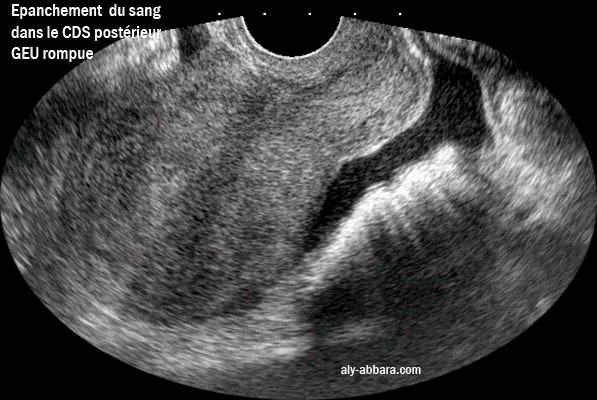

Epanchement du sang dans le cul-de-sac postérieur (de Douglas) dans le cadre d'une grossesse extra-utérine rompue

Épanchement du sang dans le cul-de-sac postérieur (de Douglas) dans le cadre

d'une grossesse extra-utérine tubaire rompue.